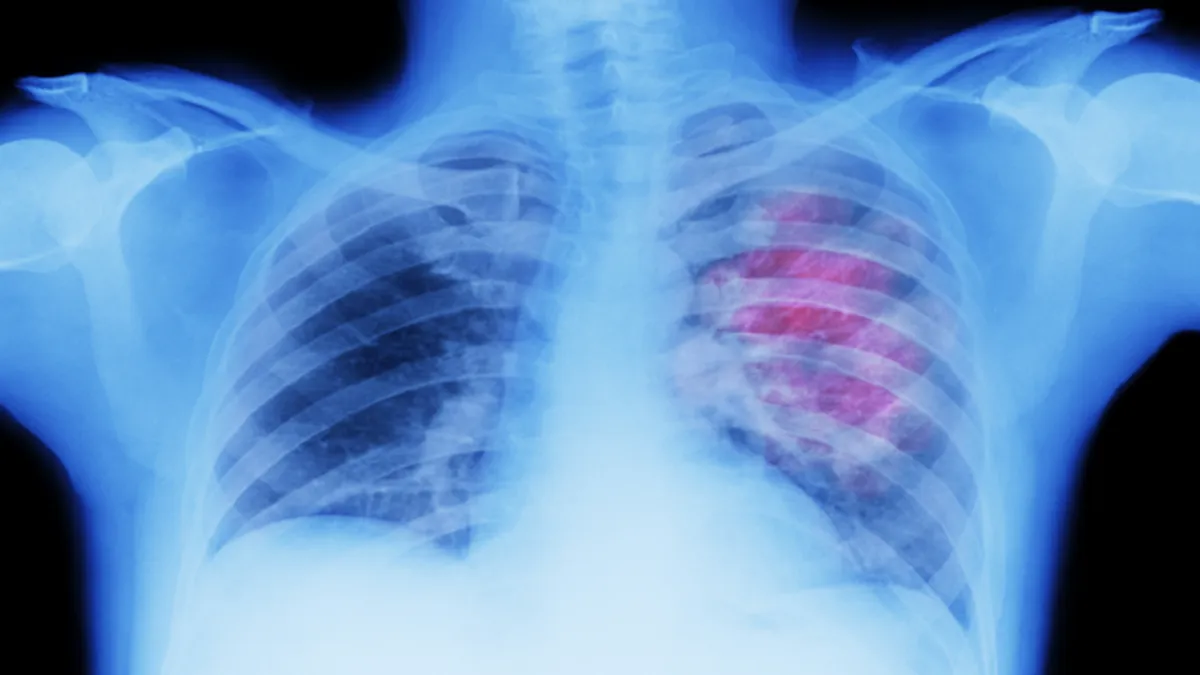

حذر خبراء من أن تورم الوجه قد يكون علامة رئيسية على الإصابة بسرطان الرئة.

أفادت وکالة آنا الإخباریة، ويمكن أن يحدث تورم الوجه، على الرغم من أن هذا السبب أقل شهرة، عندما يمارس الورم ضغطا على الوريد الأجوف العلوي (SVC)، الذي يربط الرأس بالقلب. وتجعل الجدران الرقيقة لهذا الوريد الحيوي عرضة للضغط.

ووفقا لـ Macmillan Cancer Support، فإن معظم حالات انسداد الوريد الأجوف العلوي (SVCO) ناتجة عن سرطان الرئة.

يقولون: "معظم حالات SVCO (انسداد الوريد الأجوف العلوي) ناتجة عن سرطان الرئة. قد يضغط السرطان مباشرة على SVC. أو قد ينتشر إلى الغدد الليمفاوية القريبة، والتي تصبح منتفخة. وهناك أسباب أخرى محتملة: سرطانات أخرى تصيب الغدد الليمفاوية في الصدر. وتشمل هذه الأورامَ اللمفاوية وسرطانَ الخصية والثدي والأمعاء والمريء. فتتشكل جلطة دموية في الوريد وتعوق تدفق الدم. يمكن أن يحدث هذا إذا كان لديك (خط مركزي) في الوريد - على سبيل المثال، لإعطائك علاجا كيميائيا".

وبالإضافة إلى تورم الوجه، قد يعاني الأفراد أيضا من تورم في الرقبة والذراعين وأعلى الصدر بسبب ضغط الوريد. وقد تشمل الأعراض المصاحبة الأخرى ضيق التنفس، أو الصداع، أو تغيرات في البصر، أو ظهور أوردة زرقاء على الصدر، أو الدوخة.